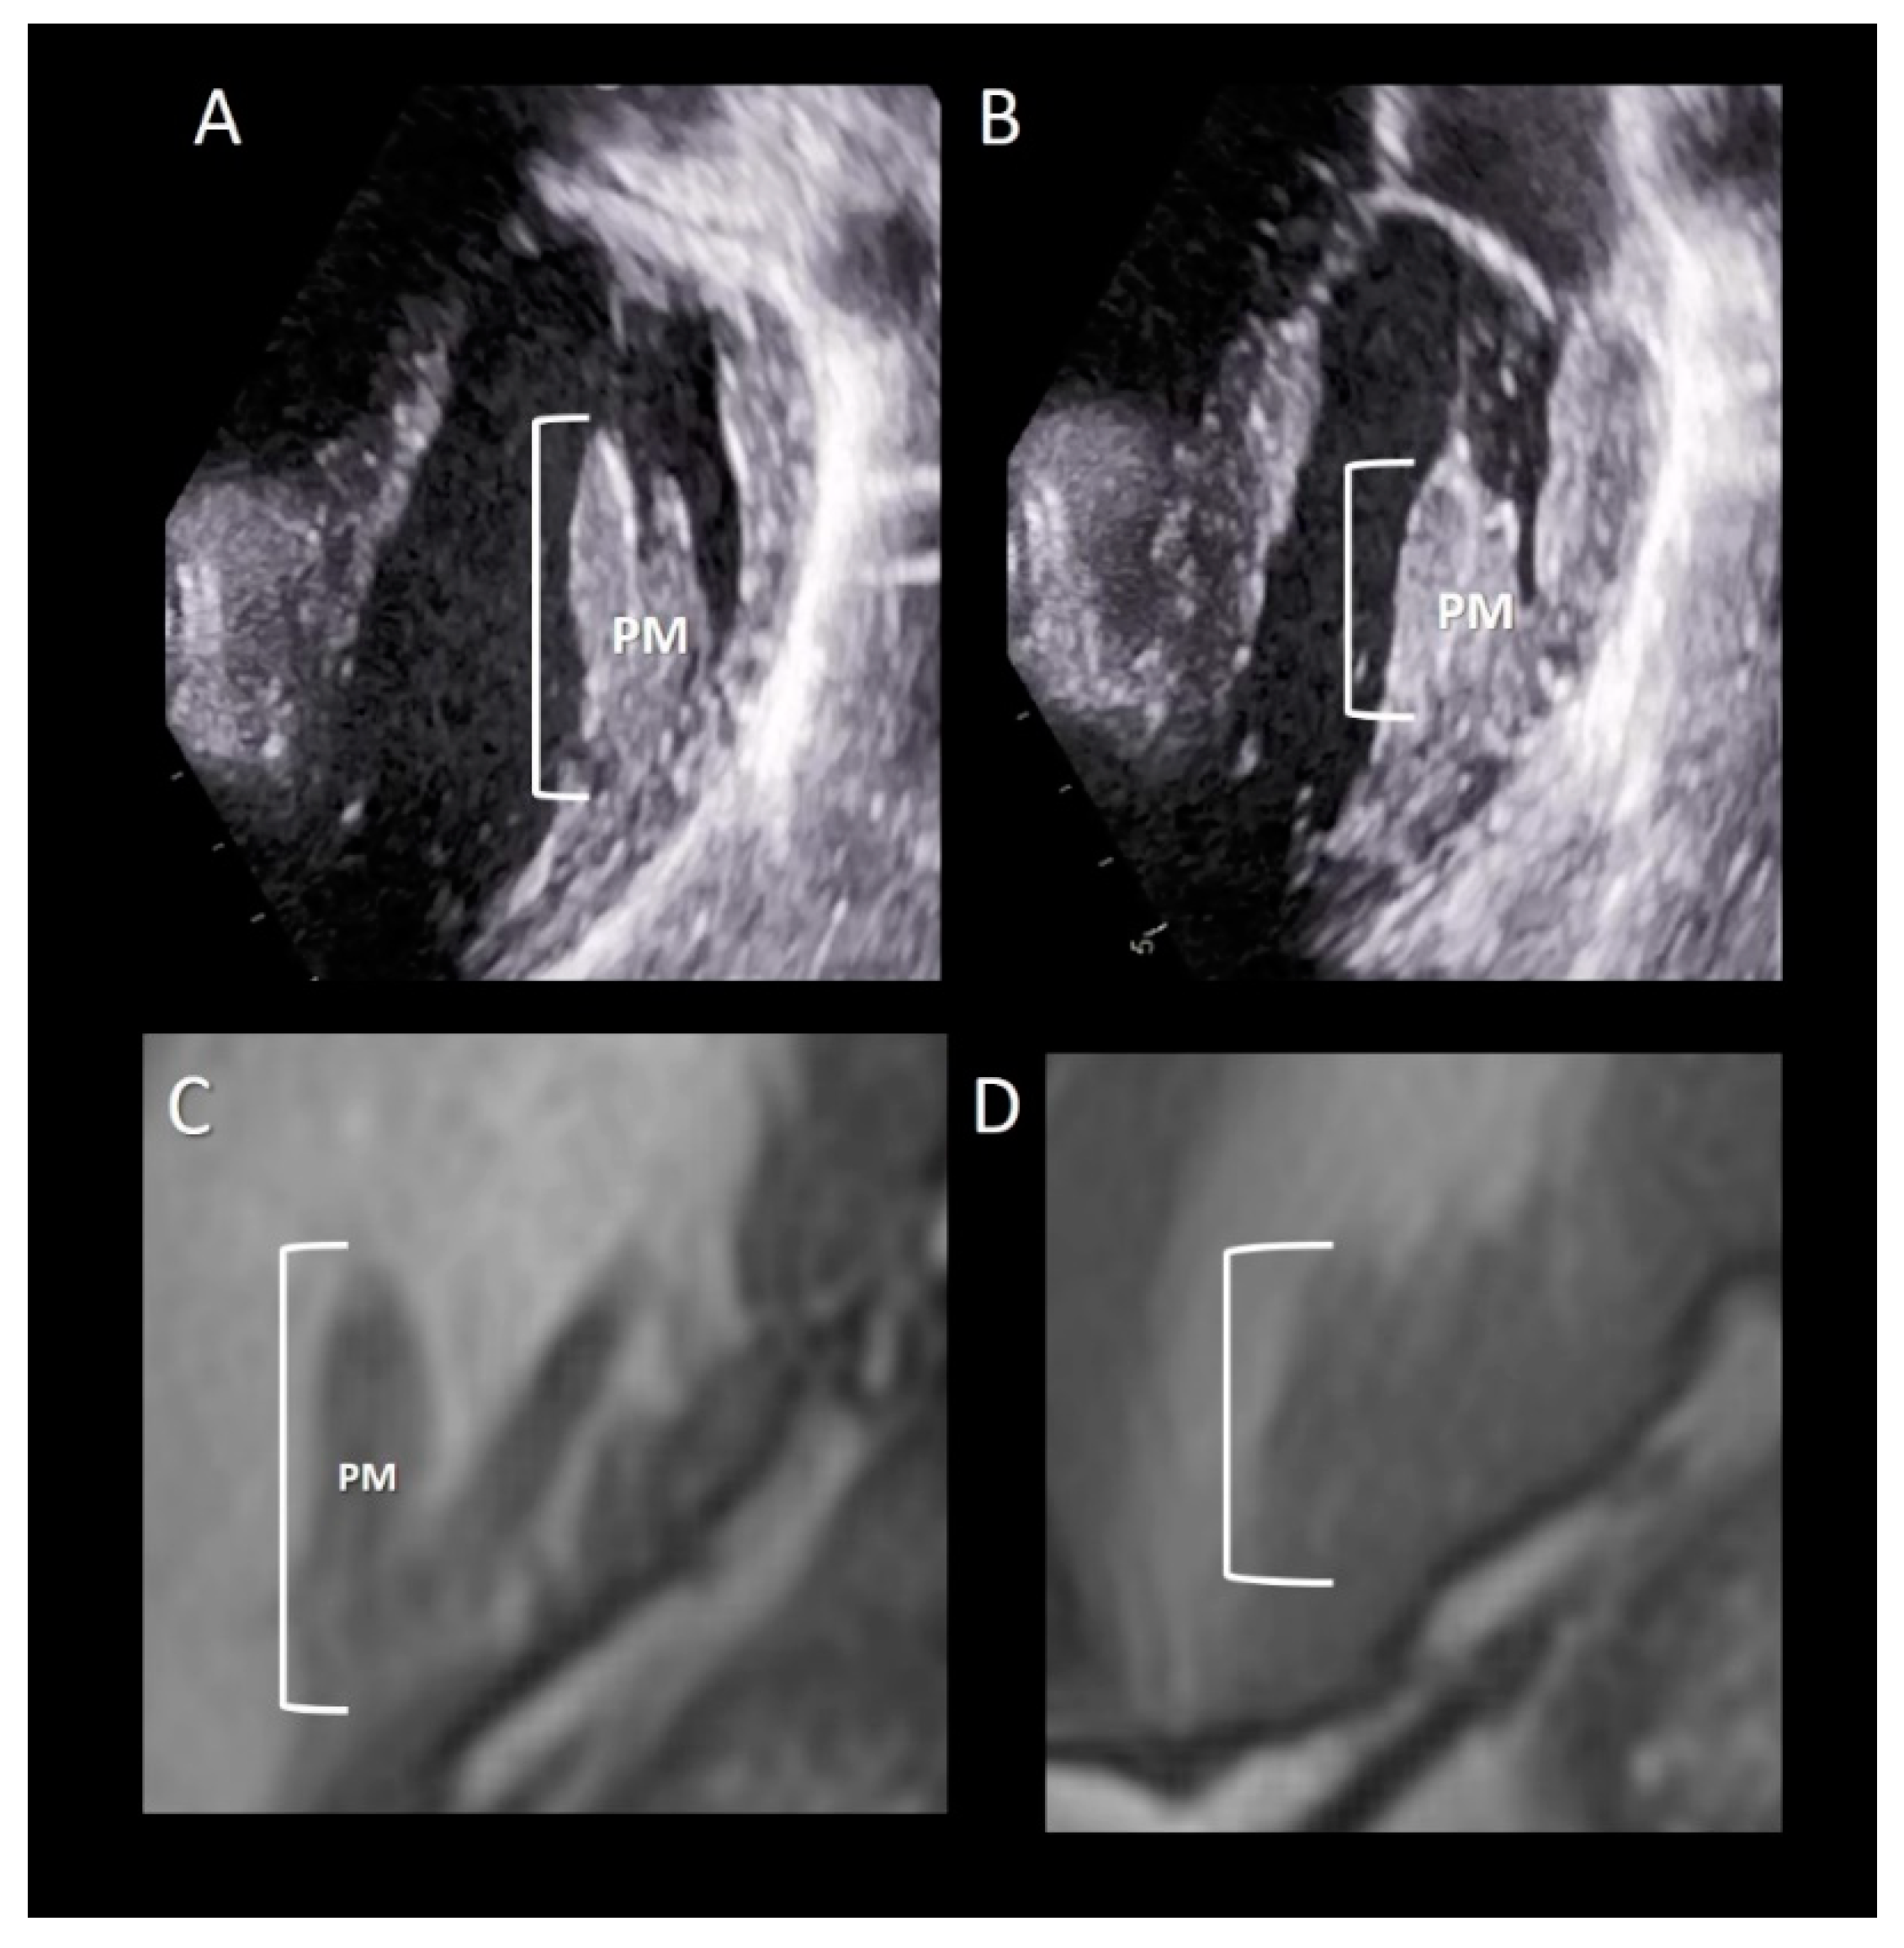

Imaging Techniques

All the three imaging modalities may beautifully illustrate PMs. Two-dimensional TTE/TEE and CMR, because of their high frame rate, may assess the shortening of the PM (Figure 8). Conversely, the high spatial resolution of CT allows for the obtaining of exceptional images of the variable anatomy of the PMs attachment on ventricular myocardium (Figure 9).

Figure 8.

(A,B) 2D TTE and (C,D) CMR cross-sections in diastole (A,C) and in systole (B,D) showing the longitudinal contraction of papillary muscle (PM) preventing leaflet eversion during the systole (see text).